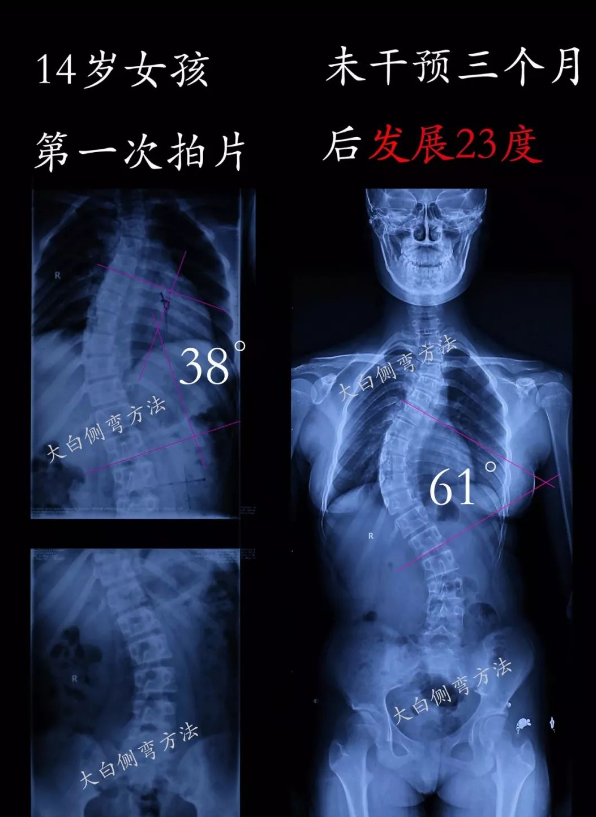

我們看到很多脊柱側(cè)彎發(fā)展的情況,例如:7天發(fā)展5度,3個(gè)月發(fā)展23度,5個(gè)月發(fā)展15度,3個(gè)月發(fā)展5度等。